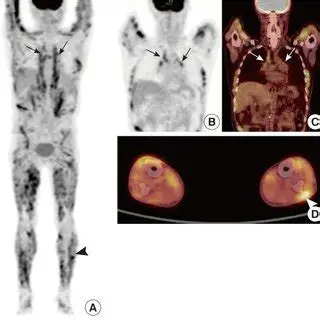

La Tomografia a Emissione di Positroni con FDG rappresenta uno strumento avanzato e fondamentale nella gestione della sarcoidosi, in particolare per i casi complessi o quando le tecniche standard (come la RX o la TC) non forniscono risposte definitive.

La FDG-PET non si limita a mostrare l’anatomia (come la TC), ma evidenzia l’attività metabolica della malattia. I granulomi attivi captano il glucosio marcato, apparendo come aree “luminose” o “calde” nelle immagini. Le sue funzioni principali sono:

- valutazione dell’attività infiammatoria: è in grado di distinguere tra infiammazione attiva (che richiede terapia) e lesioni cicatriziali o fibrotiche (che non rispondono agli antinfiammatori);

- stadiazione sistemica: essendo un esame total body, permette di individuare localizzazioni occulte della malattia in organi non sospetti, specie nel cuore nel sospetto clinico di sarcoidosi cardiaca anche se l’ECG e l’ecocardiogramma risultano negativi;

- guida alla biopsia: grazie alla sua capacità di individuare le aree a maggior attività metabolica, aiuta il chirurgo o lo pneumologo a scegliere il sito migliore per effettuare il prelievo, aumentando le probabilità di trovare granulomi;

- risposta terapeutica: la riduzione della captazione (SUVmax) alla PET dopo il trattamento (es. con Infliximab) è correlata al miglioramento della funzionalità polmonare (FVC), suggerendo che la PET sia utile per decidere se continuare o modificare le terapie in casi complessi.

Nonostante i suoi vantaggi, la PET presenta delle criticità:

- non specificità: l’aumentata captazione di FDG non è esclusiva della sarcoidosi; si verifica anche in infezioni e tumori. Ad esempio, sia i linfonodi sarcoidei che le metastasi tumorali captano il glucosio, rendendo talvolta difficile la distinzione senza una biopsia;

- reazioni sarcoidee indotte da farmaci (DISR): nei pazienti oncologici trattati con inibitori dei checkpoint immunitari (es. nivolumab, ipilimumab), la comparsa di linfonodi captanti alla PET può simulare una progressione del tumore, mentre si tratta in realtà di una reazione simil-sarcoidea.